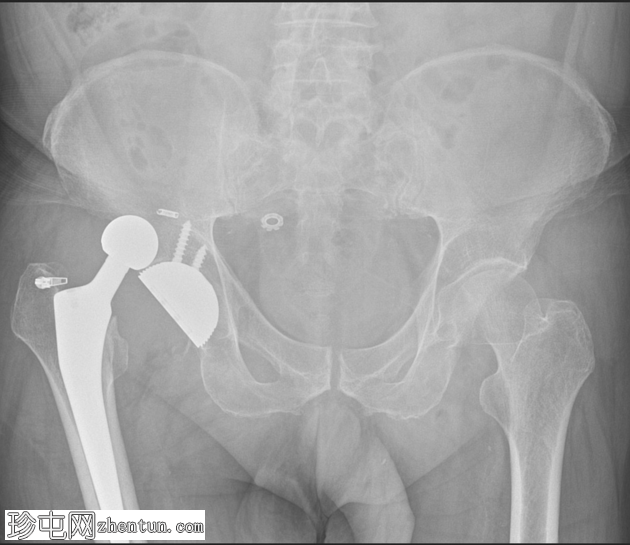

X线片

2.png

闭合复位后立即进行X线检查。

股骨假体已复位。股骨头和髋臼组件同心。

未见假体周围骨折或假体松动。